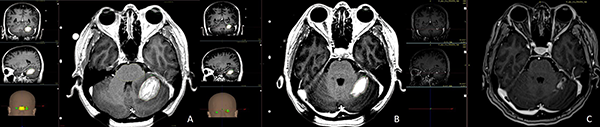

Los tratamientos con Infini™ fueron administrados a 28 (76%) pacientes, 19 (67%) de ellos en una sola fracción y 9 (32%) de ellos en protocolo de radiocirugía adaptativa, la dosis de prescripción para todo el grupo fue de 13.8 Gy (7.5-18Gy) a la curva del 50%, con dosis media en el PTV de 17.9 Gy (13.2-23.3Gy), con un volumen medio de 16.3 cc (8.5-78.4 cc). Para el protocolo de radiocirugía de dos sesiones la dosis de prescripción fue de 14.5 Gy (10-18) con una dosis media de 20.5 Gy (13.2-23-3) en la primera sesión a un volumen de 12.8 cc (8.5-78.4) y de 13.5 Gy (10-18) con una dosis media de 18.6 Gy (13-26) en la segunda sesión a los 30 días a un volumen de 4.3 cc (0.4-70) por efecto del tratamiento inicial y la consecuente reducción del tamaño tumoral (figs. 1 y 2).

Figura 1: A) Muestra una lesión metastásica de cáncer de mama en cerebelo izquierdo de 11.2 cc en volumen y se administraron 12 Gy como dosis marginal a la curva isodosica del 50% (Dosis media de 16.6 Gy). B) Segunda sesión a los 30 días en donde la lesión ha reducido su volumen a 4.9 cc representando una reducción del 56%, el efecto de masa sobre el cuarto ventrículo ha sido resuelto, se prescribió una nueva dosis de radiocirugía ahora con 15 Gy como dosis marginal a la curva isodósica del 50% (Dosis media de 19.7 Gy). C) A los tres meses la lesión mide 1.3 cc.

Figura 2:

A) Metástasis frontal izquierda de cáncer de mama con receptores hormonales negativos que produce efecto de masa midiendo en la primera sesión de radiocirugía 37 cc en su volumen inicial, la dosis de prescripción es 12 Gy a la curva del 50% señalizada en verde, la sombra anaranjada representa todo el volumen interno que está recibiendo más de 15 Gy. B) Imágenes durante el segundo tratamiento a los 30 días, el volumen de la lesión se ha reducido 62% (vol. 14cc) la nueva dosis de prescripción es 12 Gy a la curva del 50% señalizada en verde, la sombra anaranjada representa todo el volumen interno que está recibiendo más de 15 Gy. C) Control a los 3 meses, el efecto de masa ha sido resuelto por completo.